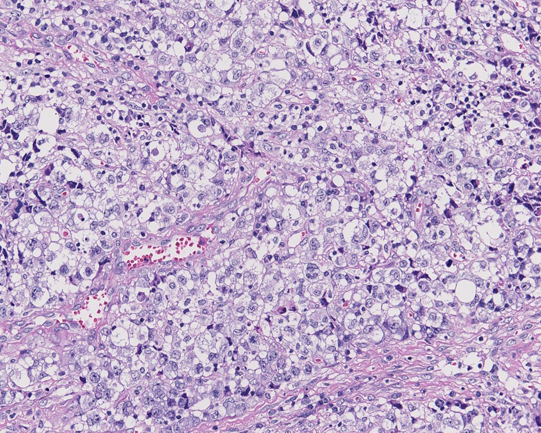

リンパ節組織所見

HE NZX2.5HE NZX10HE NZX10

大型異型細胞が集簇し結合性に増殖している。未分化癌や悪性黒色腫が鑑別となる。細胞は大型で類円形, 楕円形核に加えて腎臓様の特異な核形を示す。